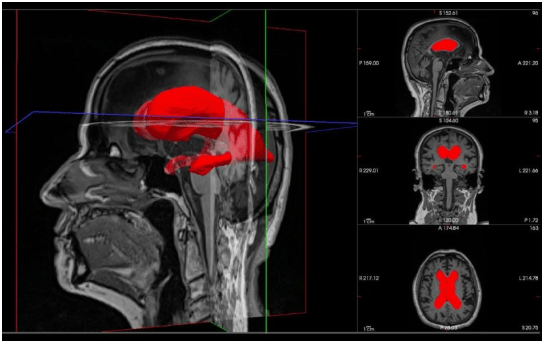

一项最新研究采用170名iNPH患者的脑部扫描数据,结合3D成像和机器学习技术,量化分析大脑侧脑室的几何特征以预测手术成功率。研究发现,几何标记物“非球面度”与更好的手术结果显著相关,为预测脑积水分流手术效果提供了新依据。

研究主要作者安德留斯·彭考斯卡斯表示:“我们的结果表明,量化脑室的3D几何形状能帮助识别可能从手术中受益的患者。这一进展有助于更精准地筛选适合脑积水分流手术的个体,避免无效治疗。”该研究由欧盟“地平线2020”计划下的玛丽·斯克沃多夫斯卡-居里行动资助。